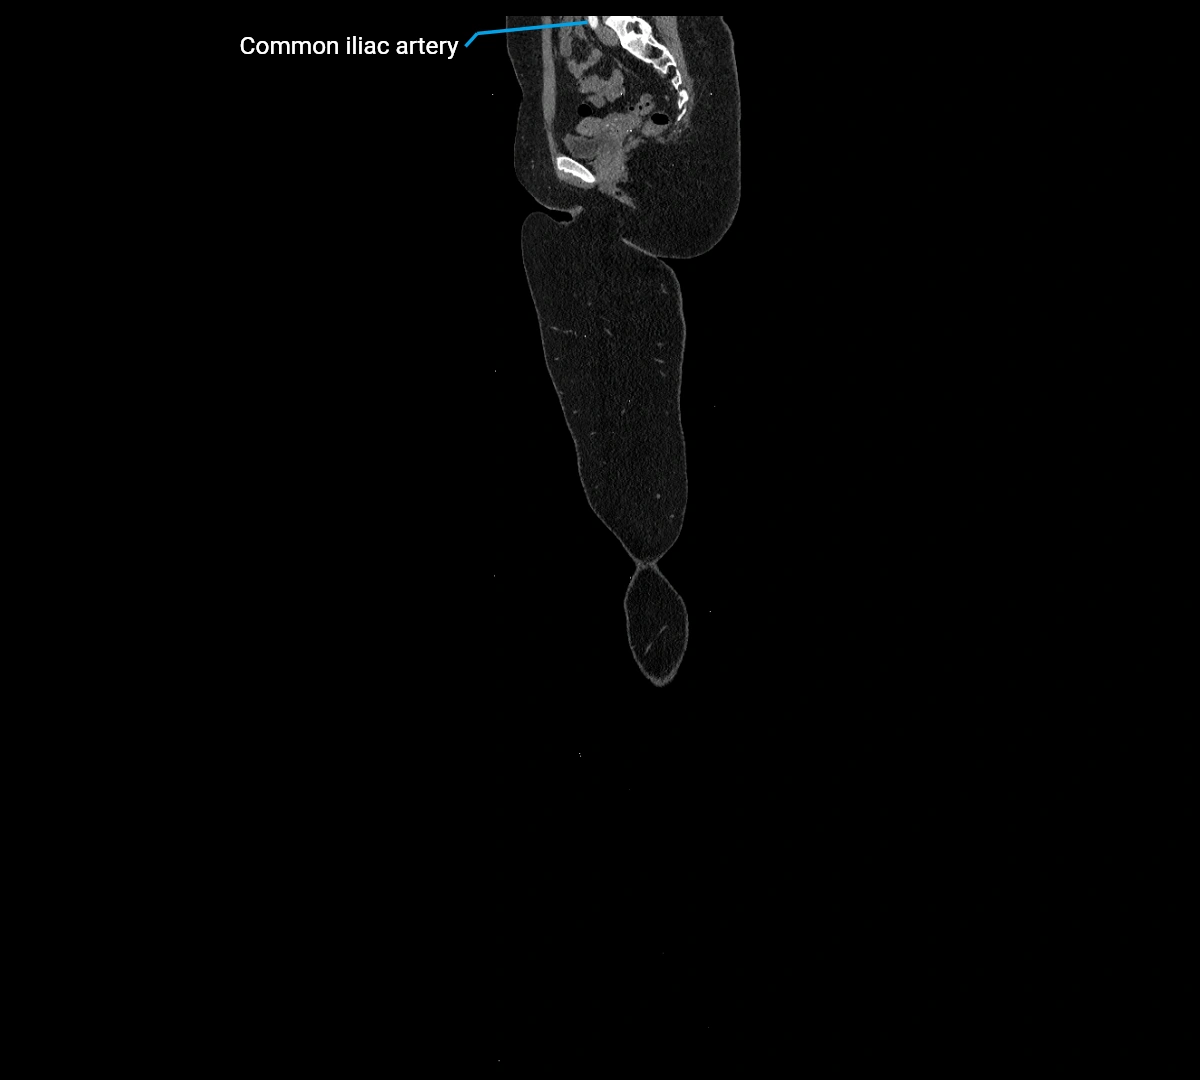

CT images

image

Contrast-enhanced CT (CTA):

• Gold standard for abdominal aortic imaging

• Provides excellent detail of lumen, wall, aneurysm, thrombus, and branch vessels

• Multiplanar and 3D reconstructions help in aneurysm measurement, stent graft planning, and dissection evaluation

• Terminal branches: right and left common iliac arteries